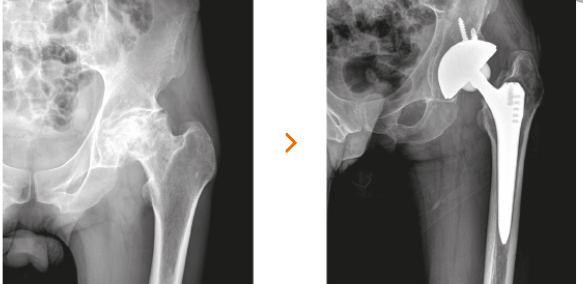

고관절 수술방법으로는 보통 3가지 방법으로 나뉩니다. 첫번째로는 대퇴골두에만 구멍을 뚫어 혈관이 생설될 수 있는 통로를 만들어 자기 관절을 살리는 감압술을 하는 방법이 있습니다.

두번쨰로는 대퇴골두에만 인공뼈를 삽입하여 치환시키는 방법과 세번째로는 관절 부분 전체를 인공관절로 바꿔주는 방법이 있습니다. 이 경우에는 심하게 괴사가 된 경우에 사용하는 방법으로 합병증이 적고 기능개선이 우수하다고 알려져 있습니다.

보통 인공관절 수술방법으로 많이들 시행합니다. 병원마다 금액이 전부 다르기 때문에 정확한 금액을 알려드릴수는 없으나, 보통 180만원 부터 250만원까지 다양하기 때문에 꼭 전문의와 상담하여 수술방법과 수술비용에 대해 상담하시길 당부드립니다.